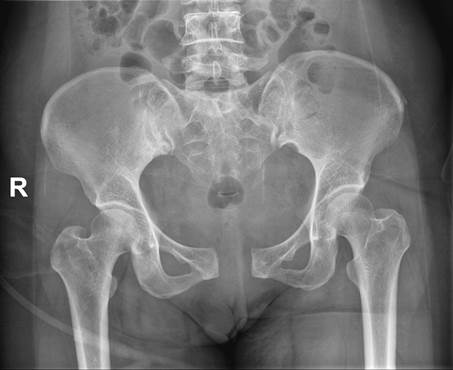

病例三:Tile B1分型,术前CT